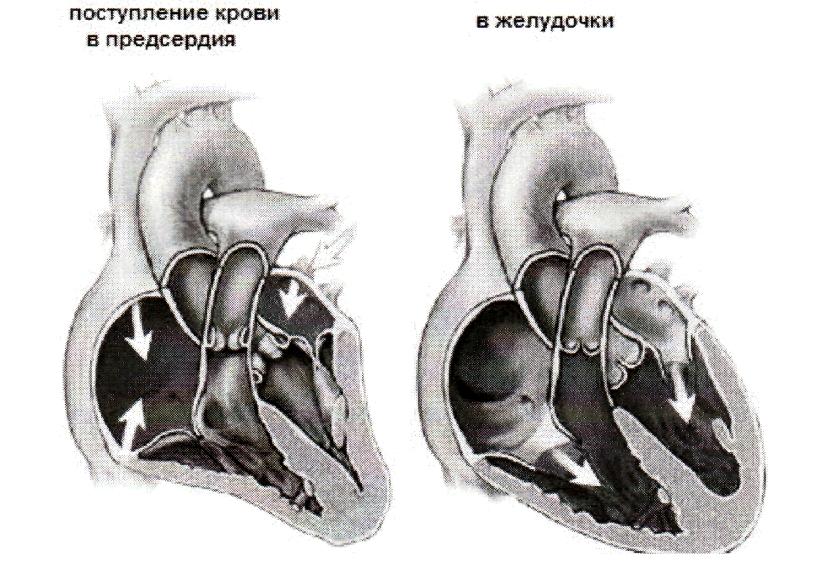

Фотографии и информация о приобретенных пороках сердца